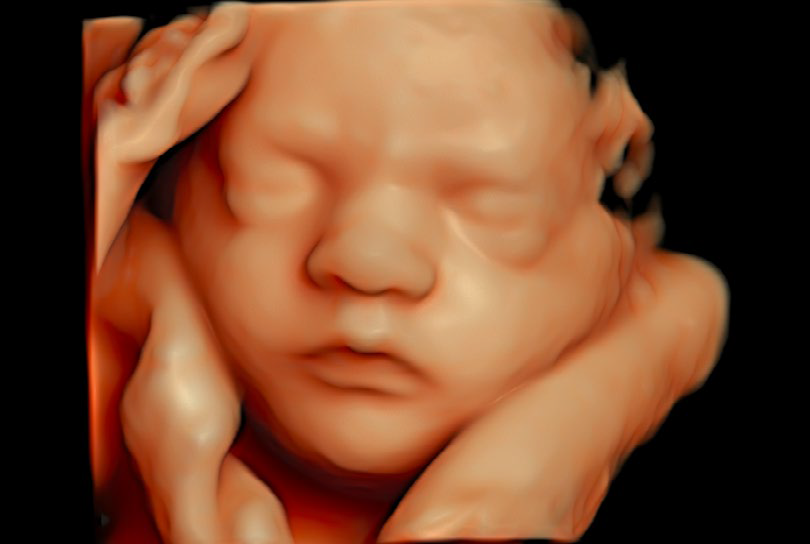

• HDliveTM technologies

El Voluson Signature 18 se basa en un nuevo motor de imágenes: la arquitectura Voluson Unity, que ofrece velocidades de procesamiento y velocidades de fotogramas más rápidas que nuestros sistemas Signature anteriores. Este hardware y software son la base del sistema y sientan las bases para las capacidades actuales y futuras. Experimente ahora un nuevo nivel de profundidad y claridad.